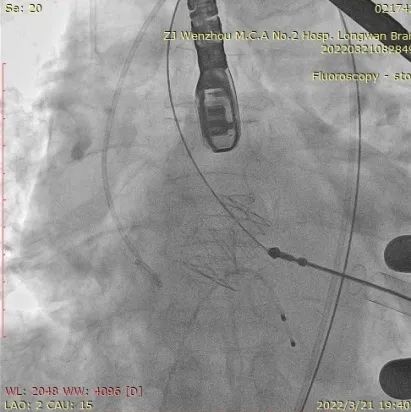

术中影像监护与评估(DSA&TEE)

瓣膜释放泥鳅导丝和单弯管过弓

加硬导丝建立轨道

介入器过瓣环平面

释放定位件

瓣膜入座

瓣膜自膨

松开锁丝,撤出输送器

DSA和TEE显示无瓣周漏,瓣膜位置、形态良好